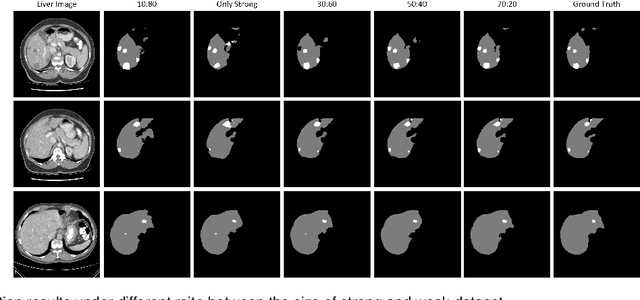

Abstract:Standard segmentation of medical images based on full-supervised convolutional networks demands accurate dense annotations. Such learning framework is built on laborious manual annotation with restrict demands for expertise, leading to insufficient high-quality labels. To overcome such limitation and exploit massive weakly labeled data, we relaxed the rigid labeling requirement and developed a semi-supervised learning framework based on a teacher-student fashion for organ and lesion segmentation with partial dense-labeled supervision and supplementary loose bounding-box supervision which are easier to acquire. Observing the geometrical relation of an organ and its inner lesions in most cases, we propose a hierarchical organ-to-lesion (O2L) attention module in a teacher segmentor to produce pseudo-labels. Then a student segmentor is trained with combinations of manual-labeled and pseudo-labeled annotations. We further proposed a localization branch realized via an aggregation of high-level features in a deep decoder to predict locations of organ and lesion, which enriches student segmentor with precise localization information. We validated each design in our model on LiTS challenge datasets by ablation study and showed its state-of-the-art performance compared with recent methods. We show our model is robust to the quality of bounding box and achieves comparable performance compared with full-supervised learning methods.